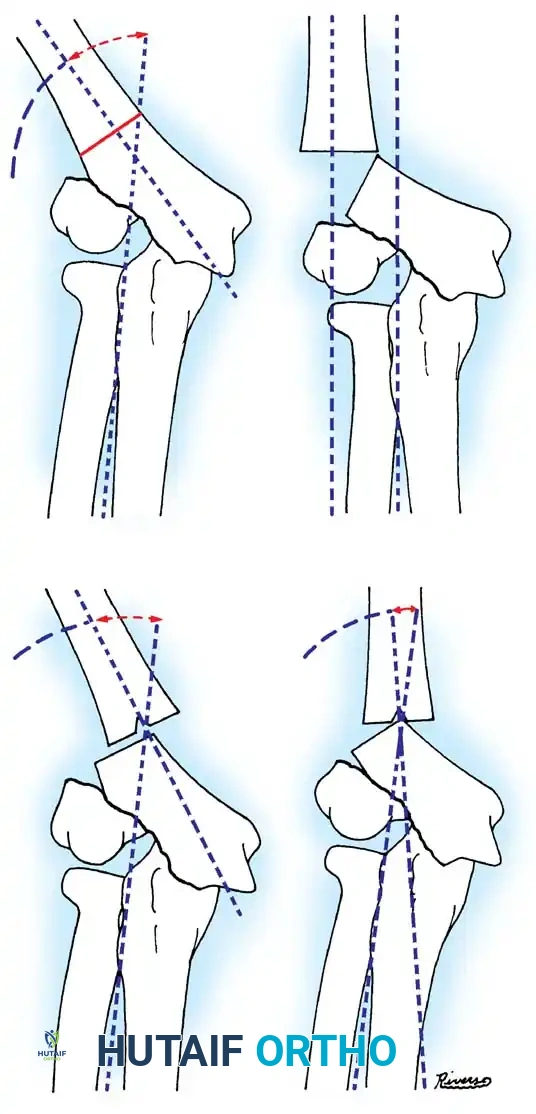

In cases of chronic radial head dislocation (often missed acutely or associated with plastic deformation of the ulna), simple open reduction is insufficient. The Hirayama Technique utilizes an ulnar osteotomy to overcorrect the angular deformity, thereby pulling the radial head back into the joint via the interosseous membrane.

TECHNIQUE 33-5: Osteotomy of the Ulna (Hirayama et al.)

- Preparation: Inflate a pneumatic tourniquet. Make a posterolateral skin incision exposing the radiohumeral joint and proximal third of the ulna. Excise intra-articular scar tissue.

- Osteotomy: Perform a subperiosteal osteotomy of the ulna 5 cm distal to the olecranon.

- Distraction and Angulation: Distract the osteotomy by 1 cm to lengthen the ulna.

- For Anterior Dislocation: Correct by posterior angulation of the ulna.

- For Lateral Dislocation: Correct by medial angulation of the ulna.

- Fixation: Secure the osteotomy with a metal plate bent to approximately 15 degrees. Ensure the radial head rests perfectly within the radial notch of the ulna without excessive radiocapitellar pressure.

- Closure: Approximate the anconeus. Do not repair the annular ligament, as this can restrict rotation.

- Postoperative Care: Apply a plaster splint in 90 degrees of flexion and full supination for 4 weeks, followed by aggressive active range of motion.

Fig. 33-36 Overcorrection with posterior convexity for anterior dislocation.

Fig. 33-37 Overcorrection with medial convexity for lateral dislocation.